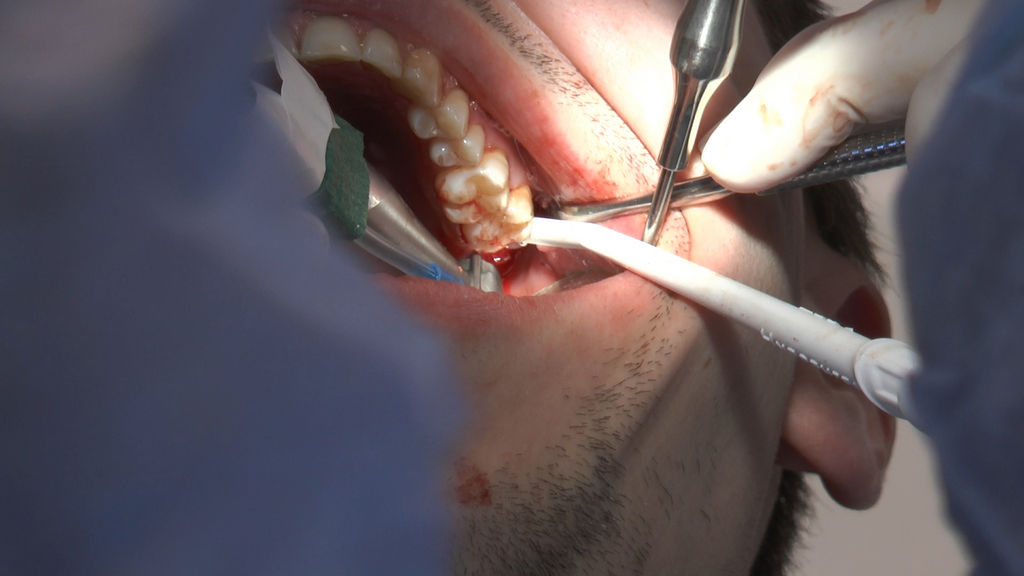

16 i 17 marca 2018 roku odbywa się VII Sesja Practiculum Implantologii Sezon V Grupa A. Jej motywem przewodnim jest chirurgia implantologiczna-kurs praktyczny z udziałem pacjentów. Lekarze wykonują procedury zabiegowe u pacjentów pod kierunkiem dr n.med. Violetty Szycik. W planie wszczepienie 34 implantów i zabiegi okołoimplantacyjne. Wszystkie zabiegi przeprowadzane są w bardzo trudnych warunkach, lecz lekarze zostali do nich doskonale przygotowani na wcześniejszych seminariach.  Fotogaleria przedstawia zabiegi wykonane drugiego dnia, w sobotę 17 marca 2018 roku.